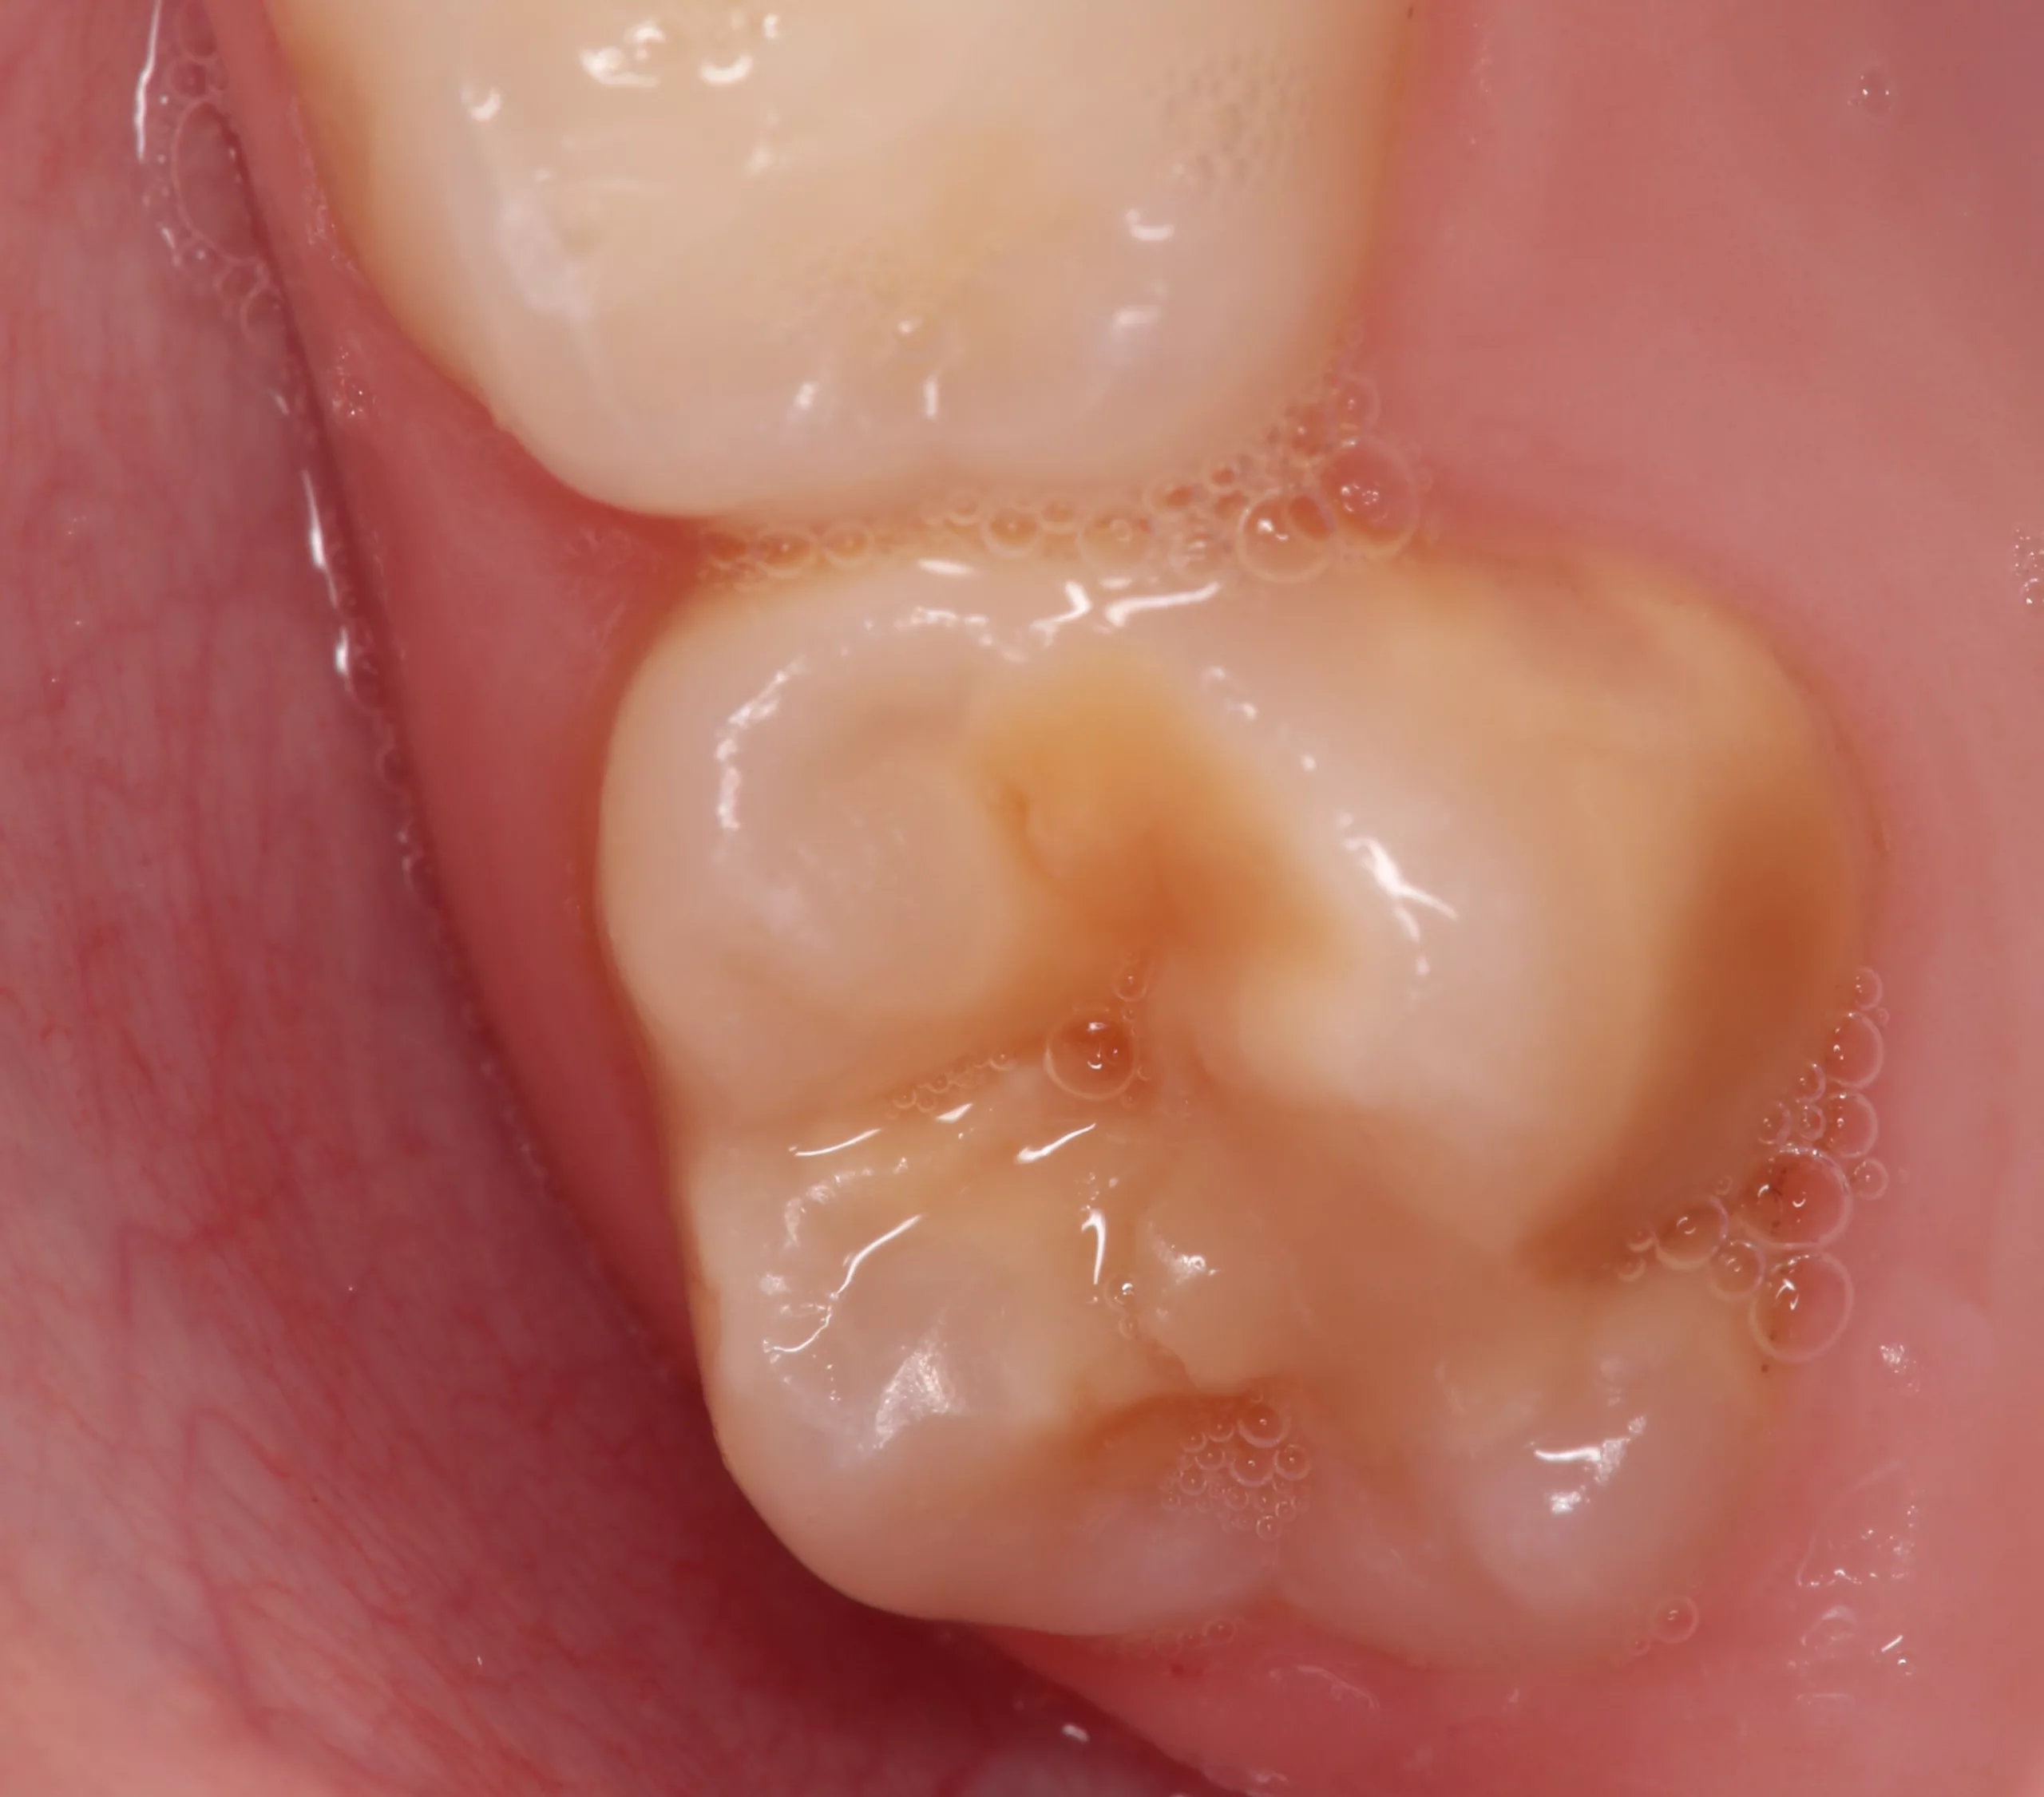

Im Alltag zeigen sich die klinischen Manifestationen von MIH in den verschiedensten Bildern und Zuständen. Für eine Einteilung in Schweregrade eignet sich die Klassifikation nach Wetzel und Reckel [19]:

- Grad I: einzelne cremefarbene bis braune Areale an Kauflächen/Höckerspitzen bei erhaltener Zahnmorphologie (Abb. 3)

- Grad II: überwiegend gelb-brauner Zahnschmelz, hypomineralisierte Bereiche über die Okklusalfläche hinaus bei erhöhter Gefahr für Schmelzfrakturen und gesteigerter Empfindlichkeit der betroffenen Zähne